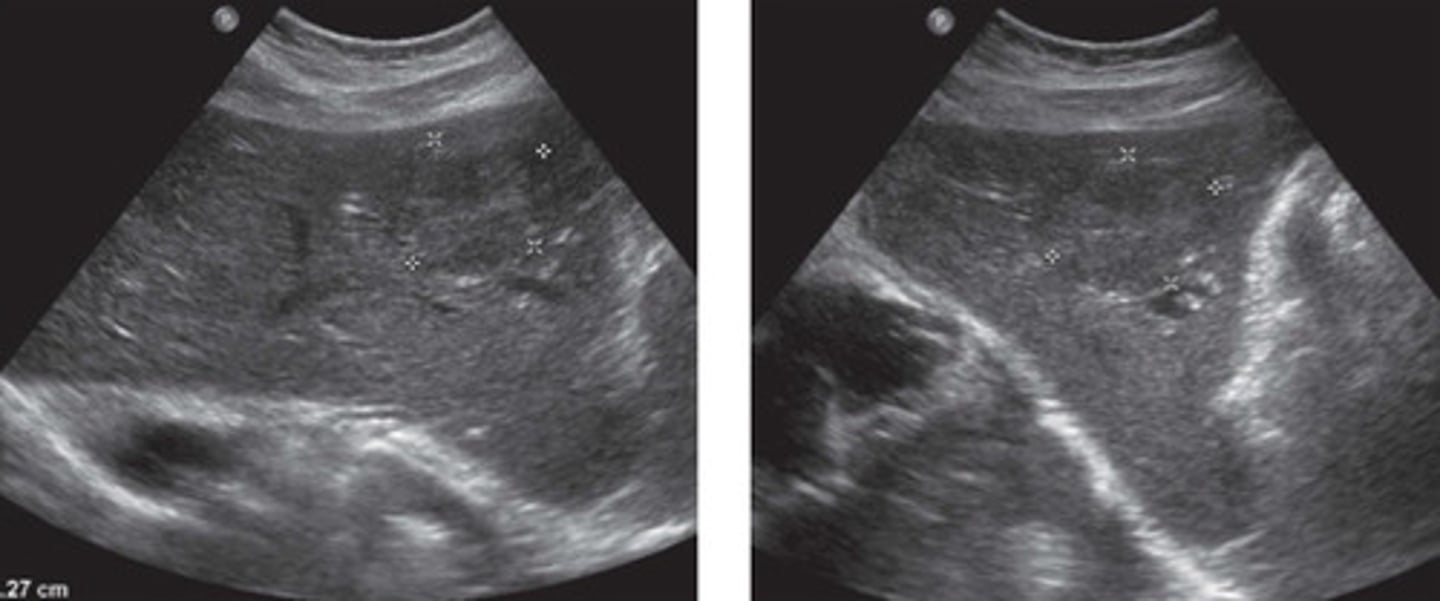

Hemangioma

What does this image show

Hemangioma (would need follow up bc bigger)

Atypical appearance of hemangioma